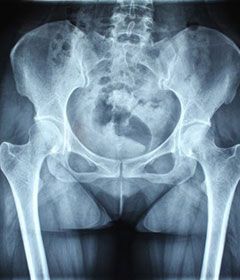

强直性脊柱炎常好发于青壮年,大部分患者病情严重时可并发髋关节病变,甚至卧床不起,生活…[详情]

强直性脊柱炎是一种慢性炎性疾病,主要侵犯骶髂关节、脊柱骨突、脊柱旁软组织及外周关节,…[详情]

治疗后骶髂关节疼痛消失,腰椎前屈、背伸侧弯活动自如,膝关节无压痛感,复查血沉、C反应蛋白、等各项检查均已达到临床康复的标准。